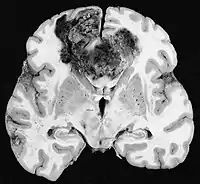

Glioblastom

De mest almindelige og maligne gliacelletumorer er glioblastomer. De består af en heterogen masse af dårligt differentierede astrocytomceller hovedsageligt hos voksne. De forekommer normalt i hjernehalvdelene, mere sjældent i hjernestammen eller rygmarven. Undtagen i meget sjældne tilfælde, som alle hjernetumorer, strækker de sig ikke ud over centralnervesystemets strukturer.

Glioblastom kan opstå fra en diffus (II. grad) eller et anaplastisk astrocytom (III. klasse) udvikle sig. I sidstnævnte tilfælde kaldes det sekundær. Men når det forekommer uden forudgående eller bevis for tidligere malignitet, omtales det som primært . Glioblastomer behandles med kirurgi, stråling og kemoterapi. De er svære at helbrede, og der er få tilfælde, der overlever mere end tre år.